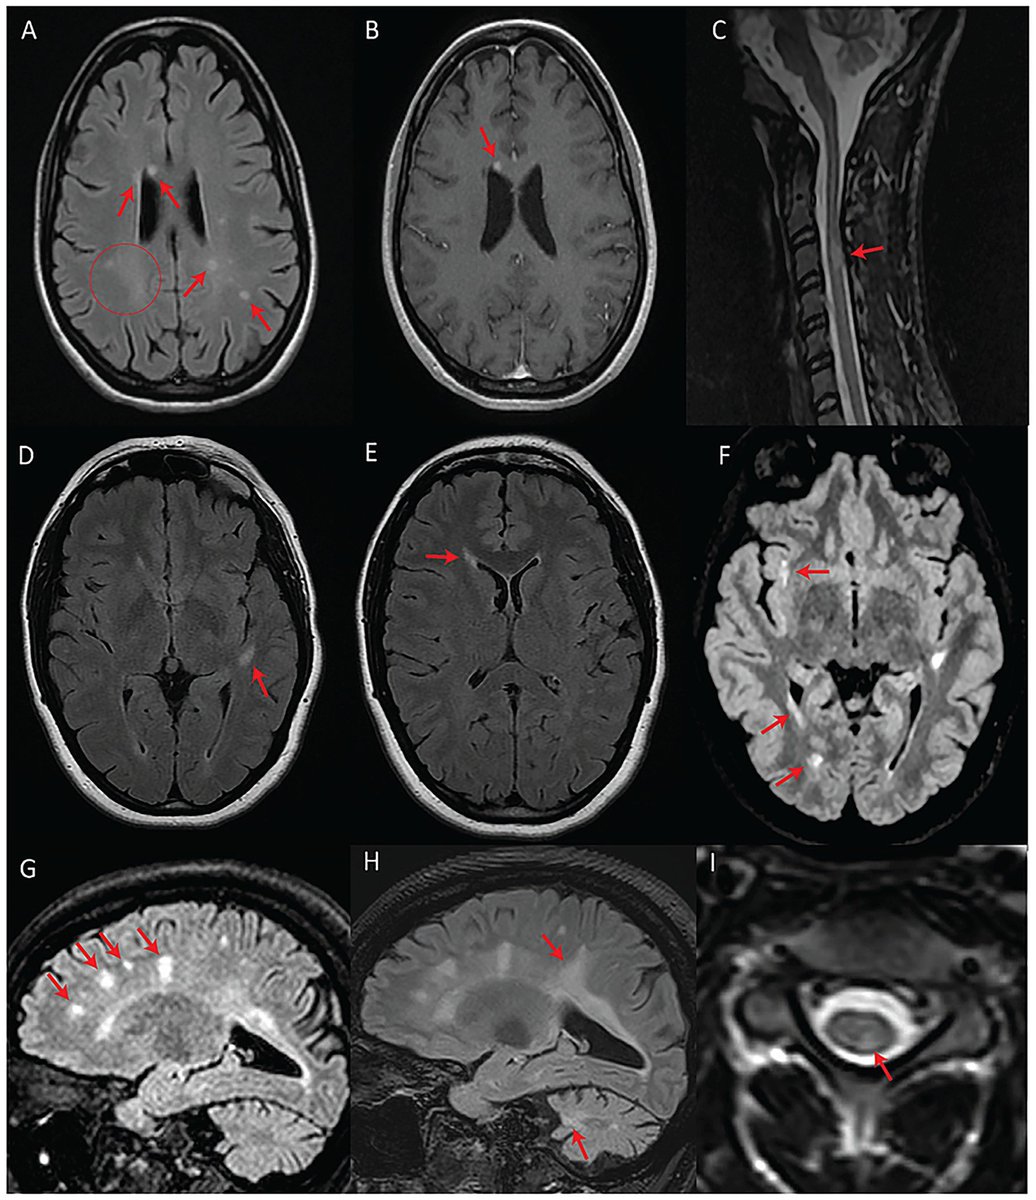

Are these MRI findings in people with multiple sclerosis?  Shockingly, NO!  They actually have Wolfram syndrome (WFS), a rare genetic disorder associated with pathogenic variants in WFS1 and is linked to optic atrophy, hearing loss and diabetes. frontiersin.org/journals/neuro…